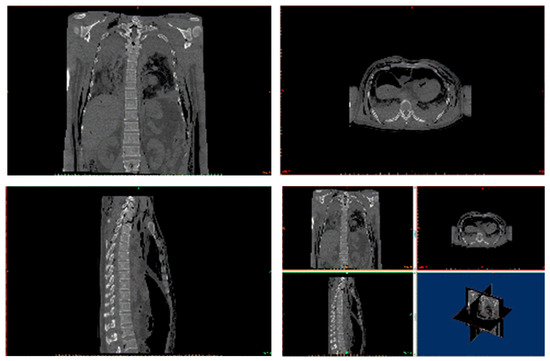

2. Background of Damaged Human Body

3. Reconstruction of the Damaged Human Model

4.1. Pre-Processing of Computational Numerical Analysis